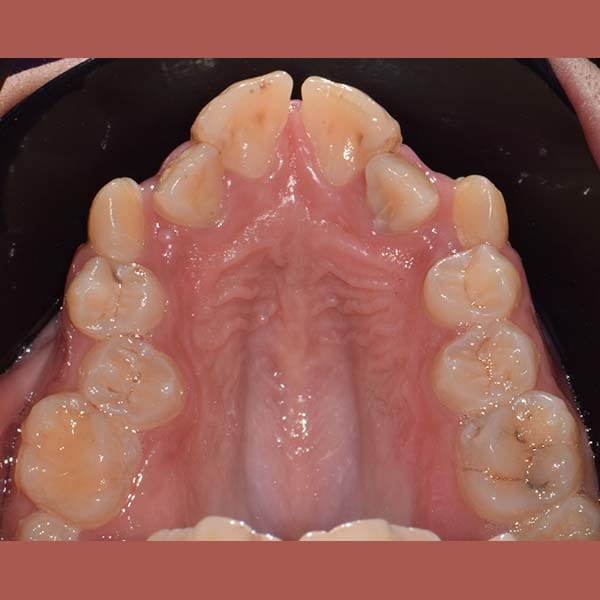

AFTER

بعد شرح أن قلع الأسنان يكون ضرورياً أحياناً، وبعد الفحص الدقيق، طمأن الدكتور خالد الكاتب الأم بأنه لحسن الحظ، حالة ابنتها تسمح بالعلاج دون قلع. اعتمدت الخطة على توسيع الفكين لفتح مسافة كافية لرصف الأسنان. تم اختيار تقويم الدايمون (ذاتي الربط) لهذه المهمة، حيث يعتبر مثالياً لهذا النوع من المعالجات التي تتطلب توسيعاً فعالاً.

كما تظهر الصور، نجحت الخطة العلاجية في رصف الأسنان بشكل ممتاز وتحقيق ابتسامة جميلة ومتناسقة. وكالعادة، أصبح بإمكان صديقتنا الشابة أن تبتسم لوالدتها ولكل من حولها بثقة وسعادة.